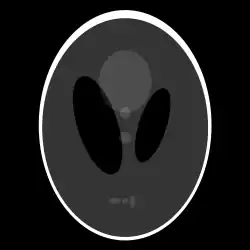

If a function represents an unknown density, then the Radon transform represents the projection data obtained as the output of a tomographic scan. Hence the inverse of the Radon transform can be used to reconstruct the original density from the projection data, and thus it forms the mathematical underpinning for tomographic reconstruction, also known as iterative reconstruction.

The process of reconstruction produces the image (or function in the previous section) from its projection data. Reconstruction is an inverse problem.

Explicit and computationally efficient inversion formulas for the Radon transform and its dual are available. The Radon transform in dimensions can be inverted by the formula:[11] where , and the power of the Laplacian is defined as a pseudo-differential operator if necessary by the Fourier transform: For computational purposes, the power of the Laplacian is commuted with the dual transform to give:[12] where is the Hilbert transform with respect to the s variable. In two dimensions, the operator appears in image processing as a ramp filter.[13] One can prove directly from the Fourier slice theorem and change of variables for integration that for a compactly supported continuous function of two variables: Thus in an image processing context the original image can be recovered from the 'sinogram' data by applying a ramp filter (in the variable) and then back-projecting. As the filtering step can be performed efficiently (for example using digital signal processing techniques) and the back projection step is simply an accumulation of values in the pixels of the image, this results in a highly efficient, and hence widely used, algorithm.